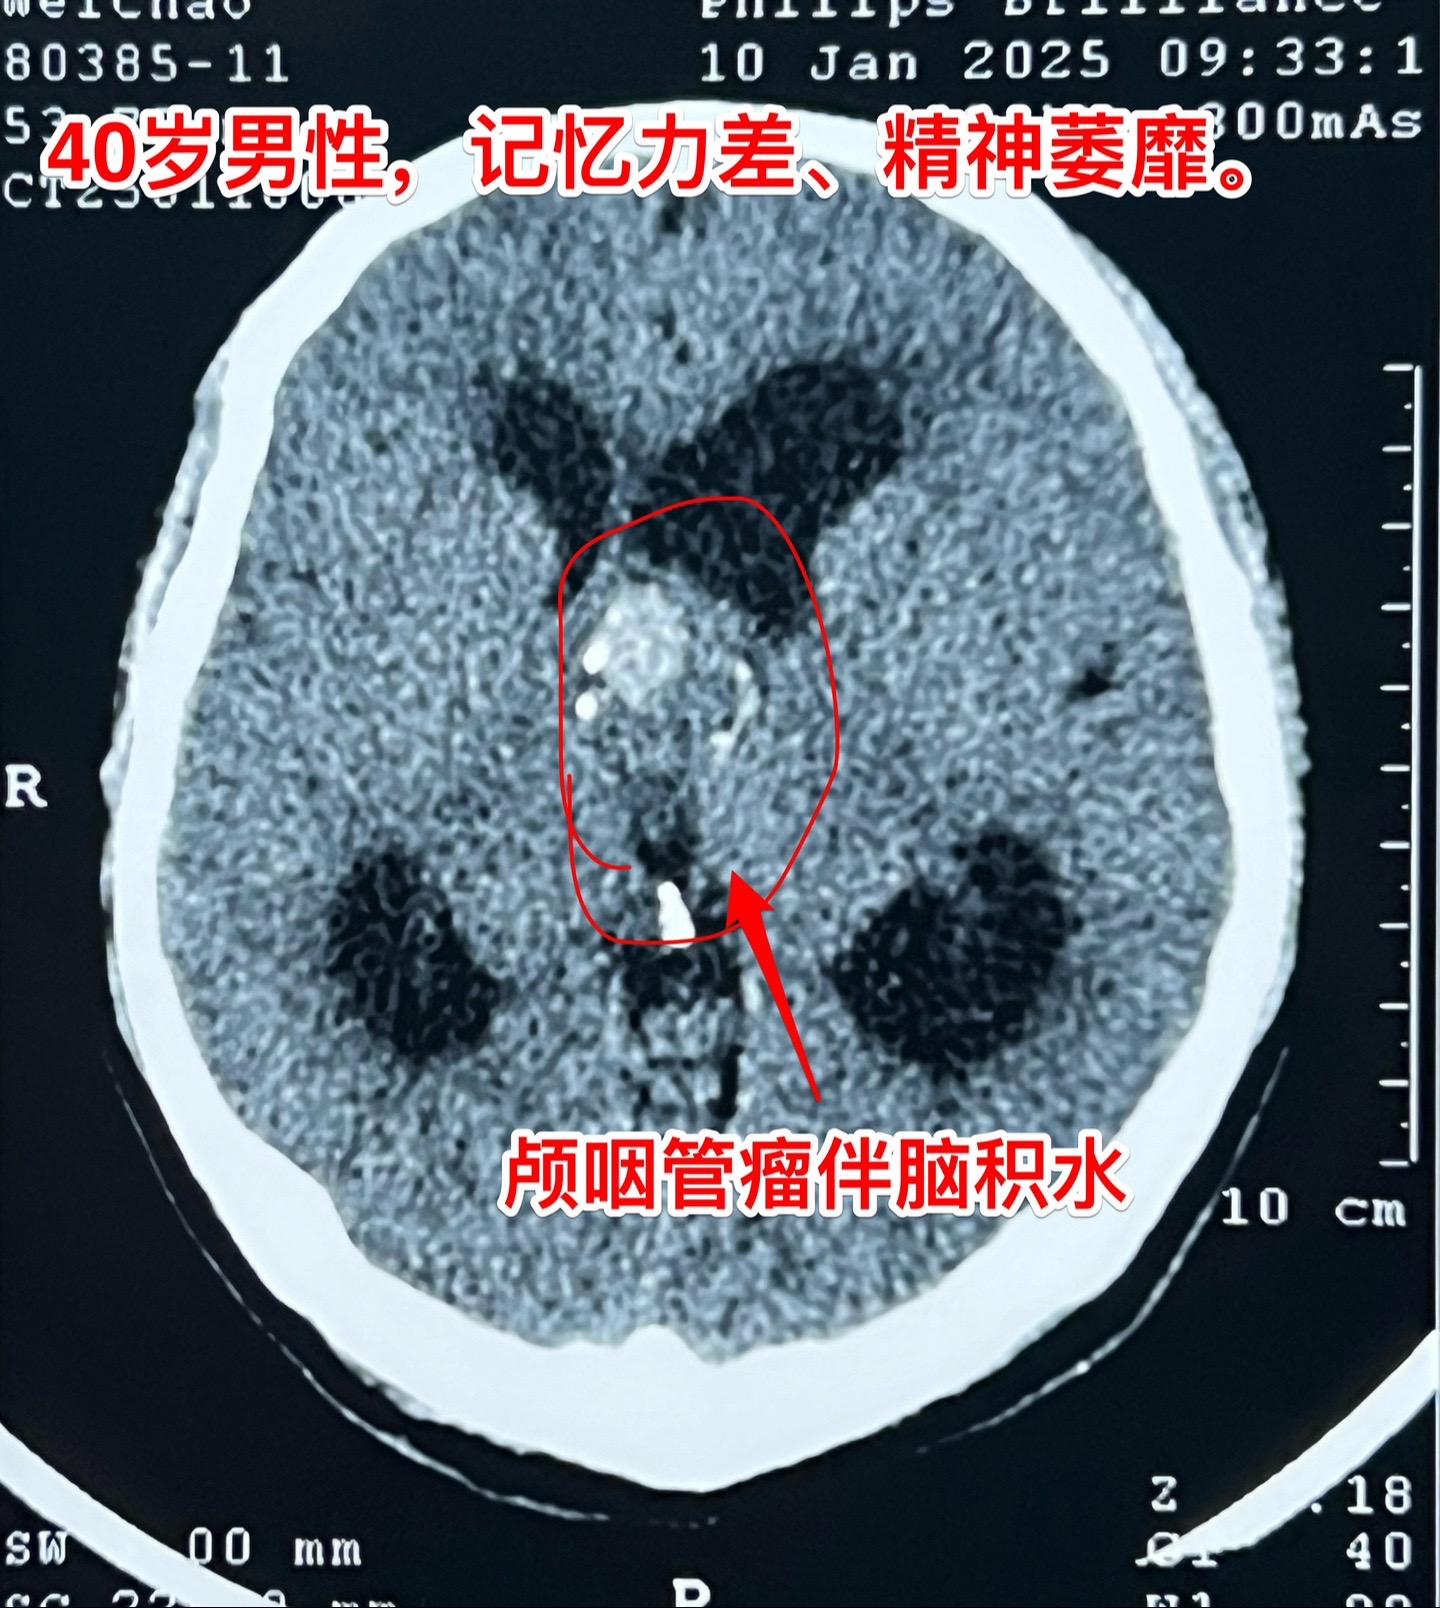

40岁男性记忆力差、精神萎靡、不能行走。患者山西省大同人,家人中有两个人是医生。一年多前患者开始出现记忆力差,没有重视。三个月前感觉精神差,2025年元旦左右症状加重,行走乏力,元月四号到医院检查脑部才发现脑肿瘤,怀疑是颅咽管瘤,伴脑积水。 元月九日到我院就诊,来的时候坐轮椅,精神萎靡,奄奄一息的样子。 元月21日作了开颅手术,肿瘤是实性的,血供比较丰富,将肿瘤完全切除。是造釉性颅咽管瘤。 病人恢复比较缓慢,但是他的状态渐渐好转起来了,计划明日出院。